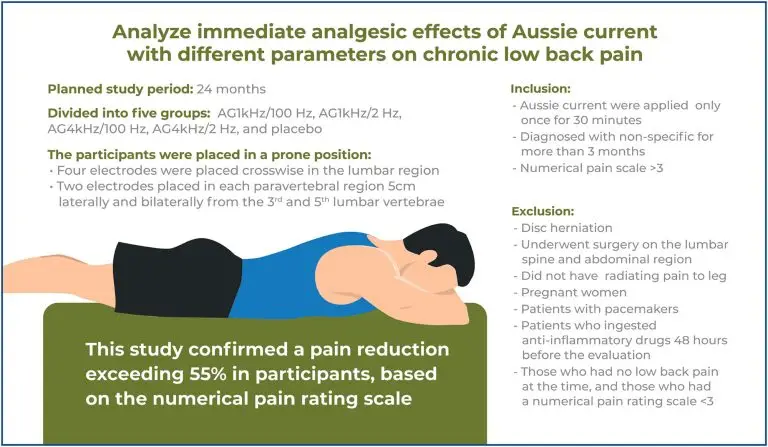

Immediate effects of Aussie Current on chronic low back pain: a randomized controlled trial

DOI: 10.31744/einstein_journal/2025AO0222

Highlights ■ Aussie Current decreases immediate pain intensity. ■ Both carrier frequencies of Aussie Current were efficient in decreasing pain. ■ There are no ideal parameters for using the Aussie Current to relieve pain in individuals with chronic lower back pain. ABSTRACT Objective: To analyze the immediate analgesic effects of Aussie Current on chronic low back pain using different parameters. Methods: A total of 105 patients (aged 18-80 years, of both sexes, with chronic low back pain) were randomized into […]

Palavras-chave: Dor lombar; Medição da dor; Estimulação elétrica nervosa transcutânea